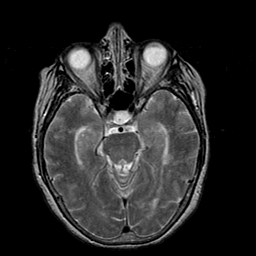

Stroke:T2-weighted MR #1 -- Slice #9

[Home][Help][Clinical] Slice 9